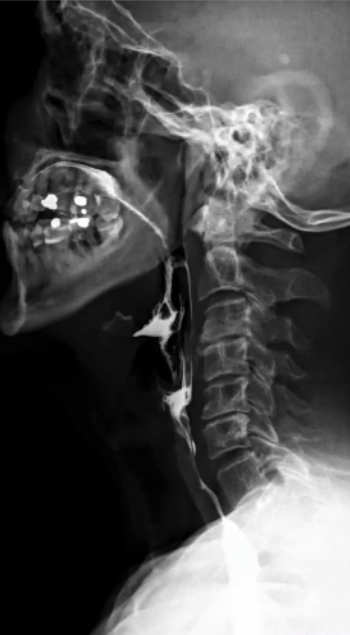

Transit oesophagien et gestro-duodénal (TOGD)

Cet examen permet de visualiser la progression d’un produit opaque au niveau de l’œsophage, de l’estomac et du duodénum et d’étudier les parois digestives.